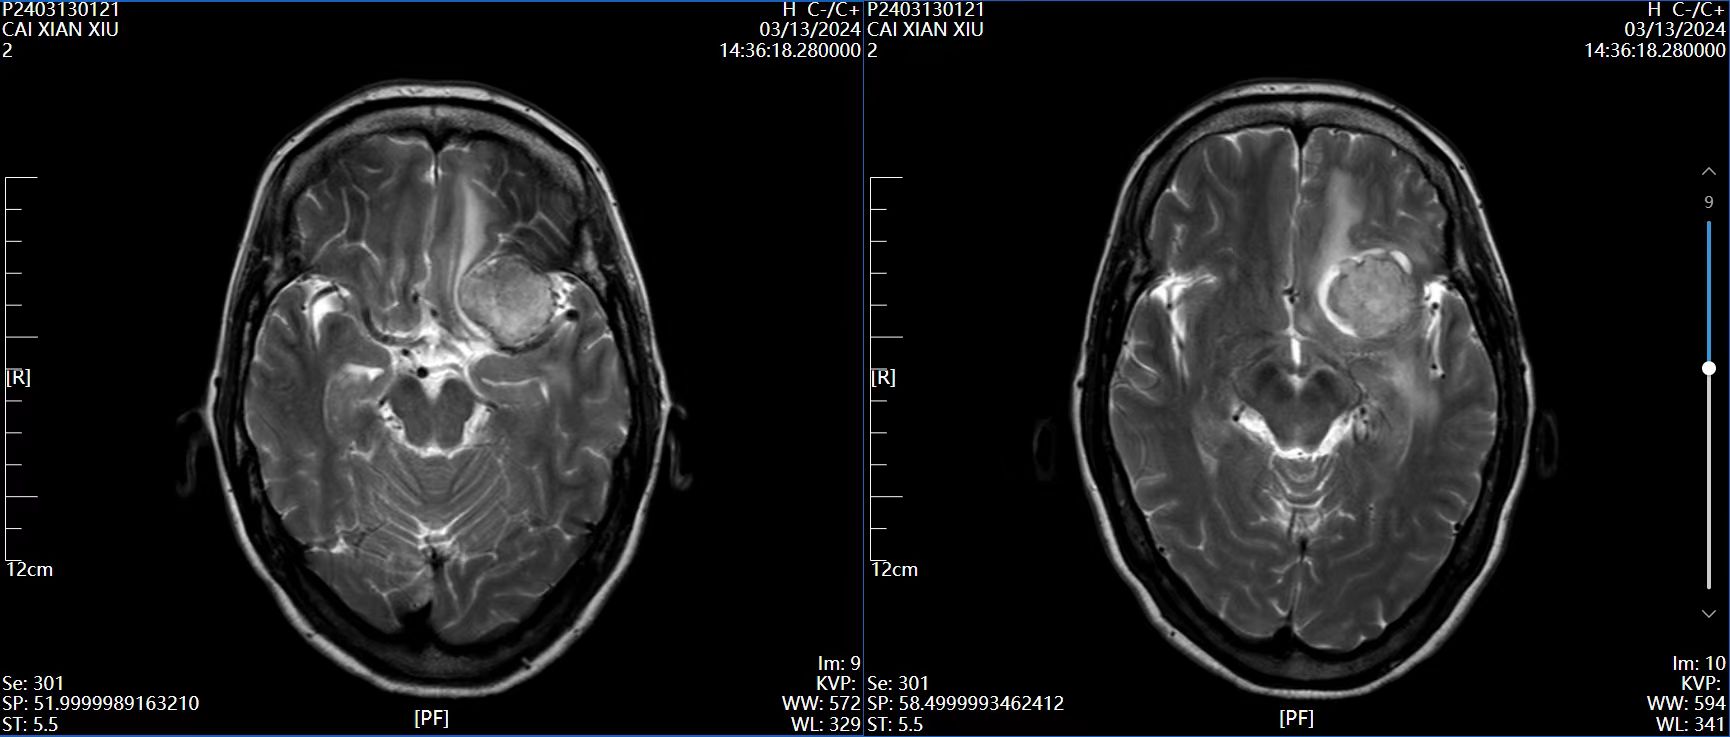

4、辅助检查:头颅磁共振检查提示:左侧前床突占位,约2.8×2.4×2.0cm大小,T1呈等低信号,T2呈等高信号,增强病灶明显强化,宽基底与前颅窝底、前床突相连,看见脑膜尾征。

磁共振T2